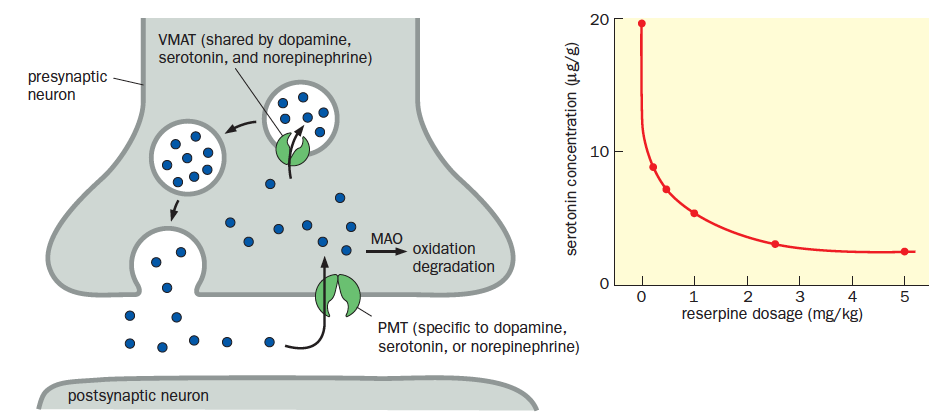

- Chlorpromazine and reserpine are drugs that alleviate positive symptoms, with side effects

- Reserpine interferes with metabolism of all three monoamine neurotransmitters– dopamine, norepinephrine and serotonin by inhibiting a vesicular monoamine transporter (VMAT) effectively depletes the levels of these neurotransmitters

VMAT is a target of anti-psychotics